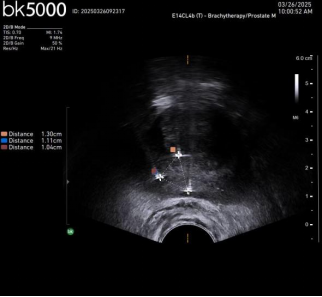

Case1. 超声定位电针穿刺及消融后改变